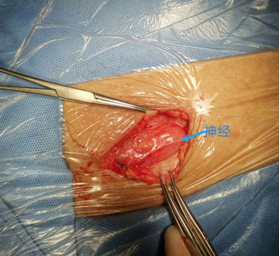

随着我们对腹股沟区解剖的深入认识,对腹股沟区神经的分布、走行有了精准定位。

手术中保护神经